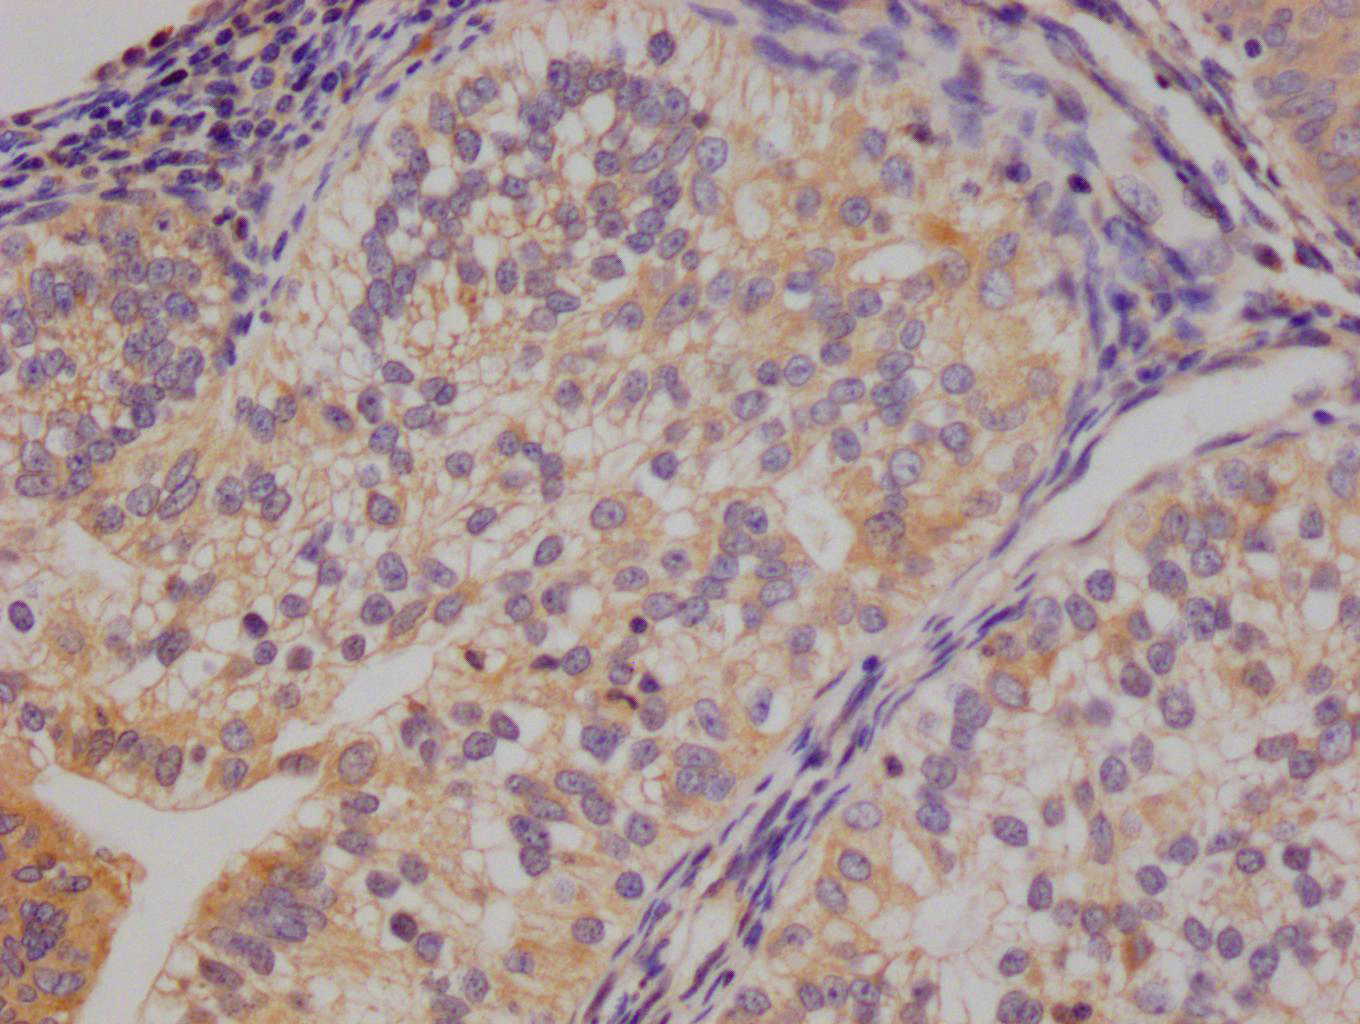

圖片:

應用范圍:ELISA, IHC

Application Recommended Dilution IHC 1:20-1:200 -